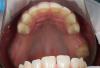

Prosthodontist Опубликовано 26 декабря, 2012 Поделиться Опубликовано 26 декабря, 2012 Аккуратненько! имплантаты можно было бы побольше углубить, учитывая будущую резорбцию на биогоризонте. Ссылка на комментарий

CSS Опубликовано 26 декабря, 2012 Автор Поделиться Опубликовано 26 декабря, 2012 Аккуратненько! имплантаты можно было бы побольше углубить, учитывая будущую резорбцию на биогоризонте.Спасибо!!! Относительно углубления, лично по моему взгляду, винт надо останавливать на 0,5 до гребня, т.к. Вроде бы к лазер-локу должна липнуть мягкая ткань. При заглублении заметил ремоделировку до 1-ГО, а иногда и до 2-ГО витка. При установке выше гребня, по моим наблюдениям, ее, ремоделировки, не происходит. Чисто суб'ективное мнение!!! На дентиуме, углубляюсь!!!;-)))) 3 Ссылка на комментарий

Mane Опубликовано 26 декабря, 2012 Поделиться Опубликовано 26 декабря, 2012 по вашему кейсы - импланты углубил бытакое впечатление что в области 25 не хватает графтаокно сделал бы меньше (есть же даск). ваш кусок может секвестрироватьсянужно стандартизировать фотопротокол а так все норм. спасибо за кейсработаю алло почти 2 годавсе нравится и ничего там не нагнаивается - для доктора шу Ссылка на комментарий